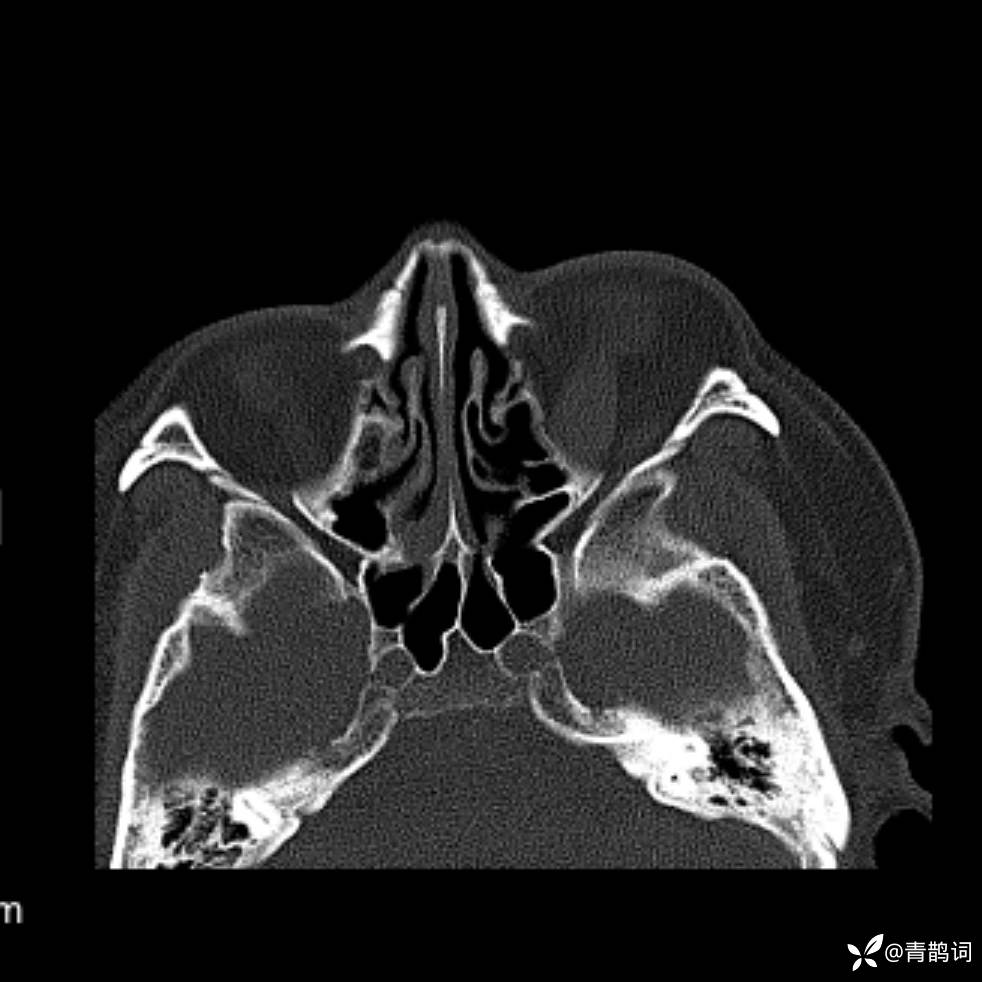

患者年龄:30岁。

患者性别:男。

简要病史:左颜面部肿胀2年,反复咳嗽咳痰,逐渐加重。

辅助检查

结合病史及影像学表现,期待评论区各位老师各抒己见~